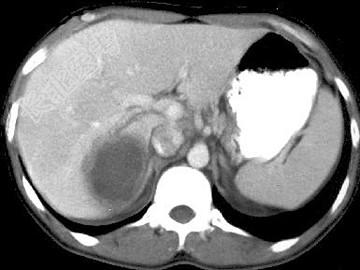

- 单项选择题女,25岁, 上腹疼痛不适,低热, 有阿米巴痢疾病史,CT检查发现肝右叶低密度病变, 如图,最可能的诊断是 ( )

D、阿米巴肝脓肿